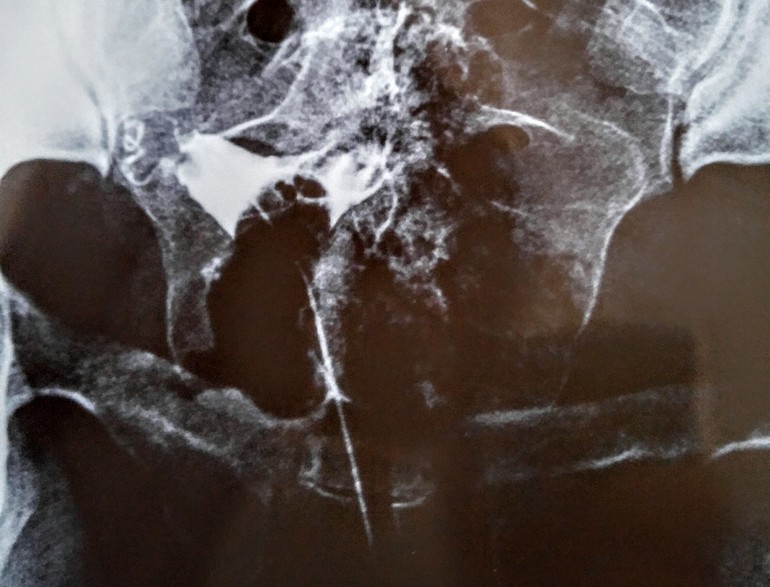

Девочки, дорогие, привет! Две недели назад сделала ГСГ, но как-то неспокойно мне. Смотрю другие снимки - там всё понятно: невооружённым глазом видно, проходимы трубы или нет. На моём же снимке - какая-то каша((( Отчётливо видно только то, что правая труба закручена, как хвостик поросёнка((( В заключении написано "частичная непроходимость обеих маточных труб". Посмотрите, пожалуйста, что думаете насчёт снимка? П.С. Врач долго не могла подобраться к матке и долго устанавливала всю эту конструкцию. После первого впрыскивания контраста, думала, что потеряю сознание от боли, всё тело непроизвольно дёрнулось.

Тут вообще картина не ясная... матка где то сбоку...

Очень плохое качество снимка.

Про то, что труба закручена, ничего не говорили?

У меня по ГСГ правая труба вообще как спираль закрученная была. Врачи сказали, типа раньше такого не видели и это не очень.

Не снимок, а какой-то треш! У вас он только 1? У меня просто 3 было.

Да, обе БхБ подтверждались ХГЧ. Диагноз официально ставил врач. А рентген похож на мясорубку)))

Ирэн, ой, забыла написать, что было 4 снимка, но этот самый удачный.

не вижу, что проходимы

растекания реагента нет по полости в обоих случаях.